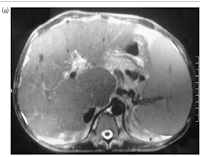

These findings were confirmed on MRI of the liver . These features were consistent with Budd Chiari Syndrome. MR venography confirmed nonvisualization of hepatic veins with patent inferior venacava (Fig. 1a and b).